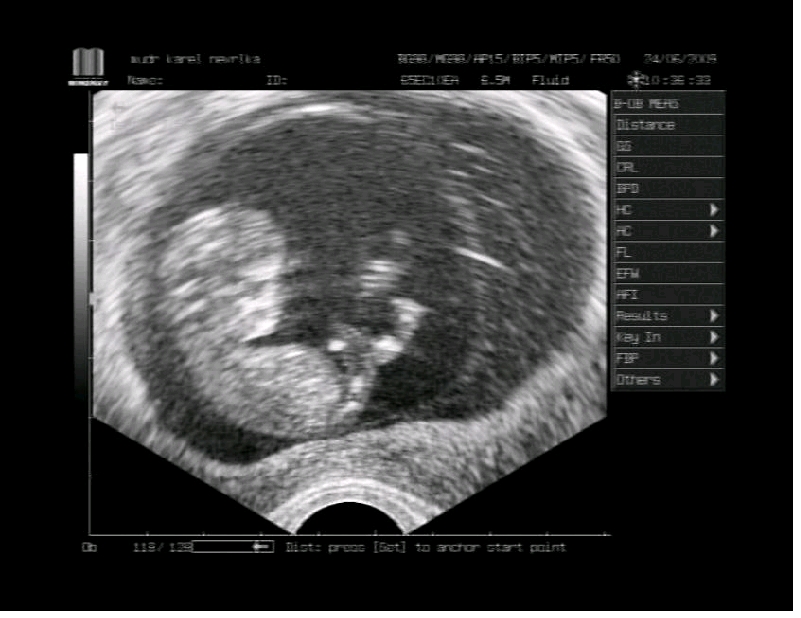

11tt+3